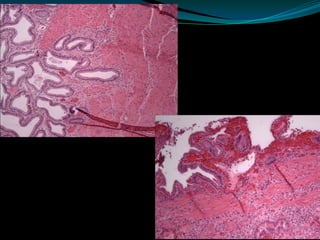

VESICULA BILIAR CON COLECISTITIS

CRONICA, COLELITIASIS

Y UN PEQUEÑO TUMOR PAPILAR A NIVEL DEL

CONDUCTO CISTICO (macro)

Adenocarcinoma Papilar de la Vesícula Biliar

(micro)

VESICULA BILIAR CONCOLECISTITIS CRONICA, COLELITIASIS Y UN PEQUEÑO TUMOR PAPILAR A NIVEL DEL CONDUCTO CISTICO (macro) Adenocarcinoma Papilar de la Vesícula Biliar (micro)